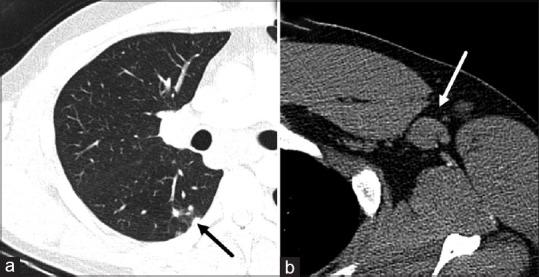

儿童间质性肺疾病:基于病例的影像学表现综述

Childhood interstitial lung disease: A case-based review of the imaging findings.

Childhood interstitial lung disease (chILD) consists of a large, heterogeneous group of individually rare disorders. chILD demonstrates major differences in disease etiology, natural history, and management when compared with the adult group. It occurs primarily secondary to an underlying developmental or genetic abnormality affecting the growth and maturity of the pediatric lung. They present with different clinical, radiologic, and pathologic features. In this pictorial review article, we will divide chILD into those more prevalent in infancy and those not specific to infancy. We will use a case based approach to discuss relevant imaging findings including modalities such as radiograph and computed tomography in a wide variety of pathologies.

摘要

儿童间质性肺疾病(chILD)由一大组种类繁多、各自罕见的疾病组成。与成人组相比,chILD在疾病病因、自然史和治疗方面存在重大差异。它主要继发于影响小儿肺部生长和成熟的潜在发育或基因异常。它们具有不同的临床、放射学和病理学特征。在这篇图片综述文章中,我们将把chILD分为在婴儿期更常见的疾病和并非婴儿期特有的疾病。我们将采用基于病例的方法来讨论相关的影像学表现,包括在各种病理情况下的X线片和计算机断层扫描等检查方式。